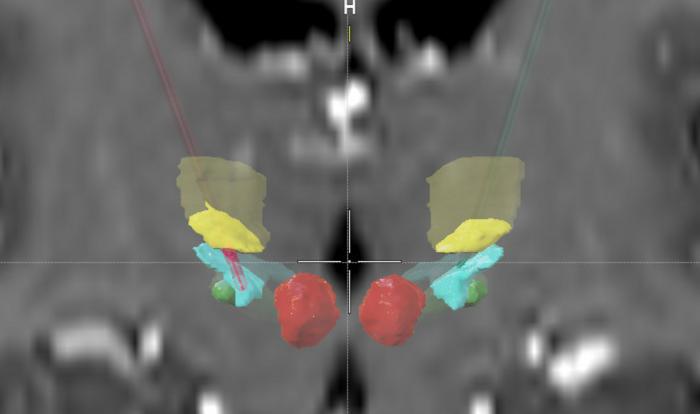

Position of the implanted electrodes in the patient’s basal ganglia.

The position of the implanted electrodes in the patient’s basal ganglia.

Credit: Kell et al., J Fluency Dis 2025, doi: https://doi.org/10.1016/j.jfludis.2025.106147

Following extensive scientific preparation and at the patient’s repetitive request, the teams from Frankfurt and Münster implanted a hair-thin wire into the left thalamus of a man who stutters. The thalamus is a central relay station deep within the brain. Through this wire, the brain region was stimulated with mild electrical currents. Standardized tests were then used to measure how the patient’s stuttering changed.